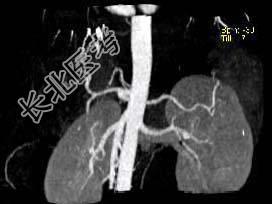

- 单项选择题结合图像,最可能的诊断为 ( )

A、胰腺癌

B、胰岛细胞癌

C、胰腺囊腺癌

D、胰腺炎

E、以上都不是